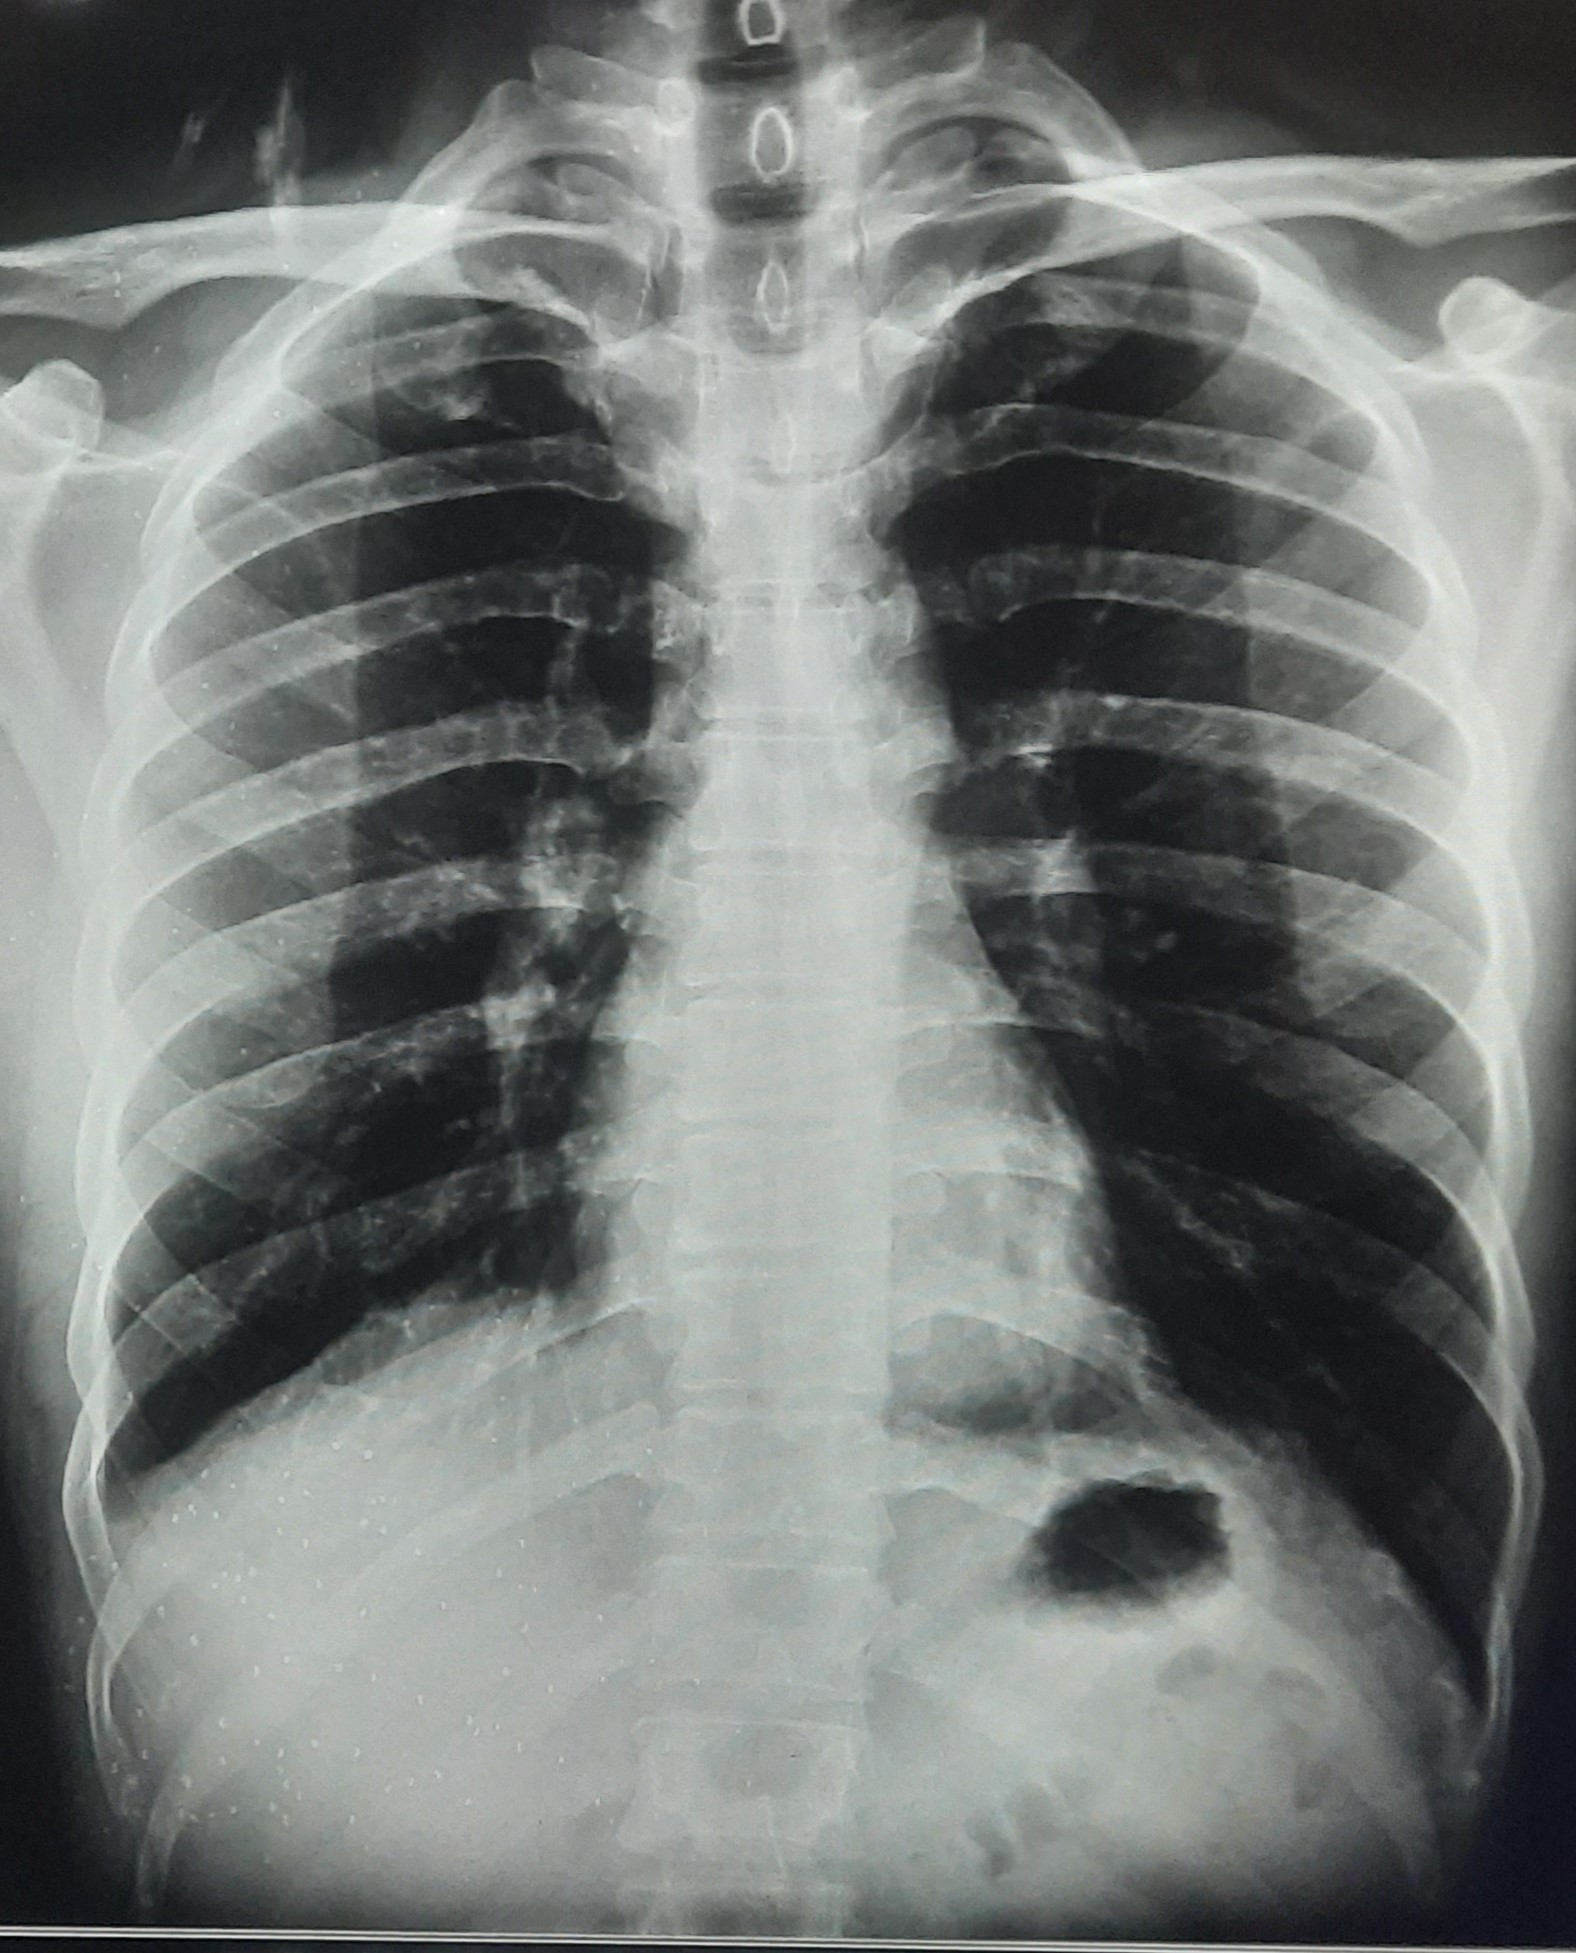

| 205 | IGGMC, Nagpur, Nagpur | P2 | 29-4267 | MOHAMMAD HANIF SUREYYA | Consent taken on Paper | 55 Yrs. |

Provisional Diag : PTB?

Final Diag : PNAEMOTHORAX /CLINICALLY DIAGNOSED PTB |

TB Case (Confirmed) | LEFT SIDED PNAEMOTHORAX | Abnormality visible on x-ray |